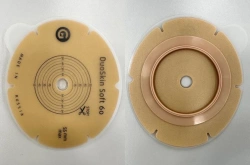

Medical product is intended for use in colostomies, ileostomies and urostomies for hermetic and secure attachment of stoma bags to the skin of the anterior abdominal wall, as well as to protect the skin of the peristomal area from stoma secretions and preserve the physiological functions of the skin due to the absorption of natural skin moisture (sweat, sebum).